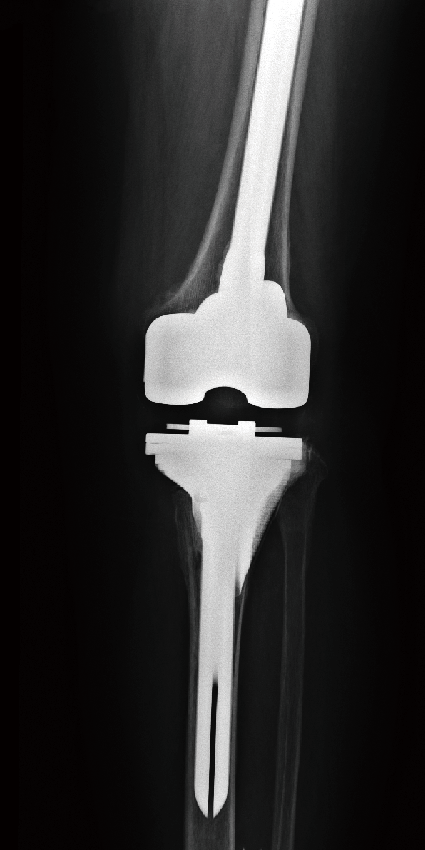

单髁翻修

单髁膝关节置换术后8年,塌陷,接受全膝关节表面置换术